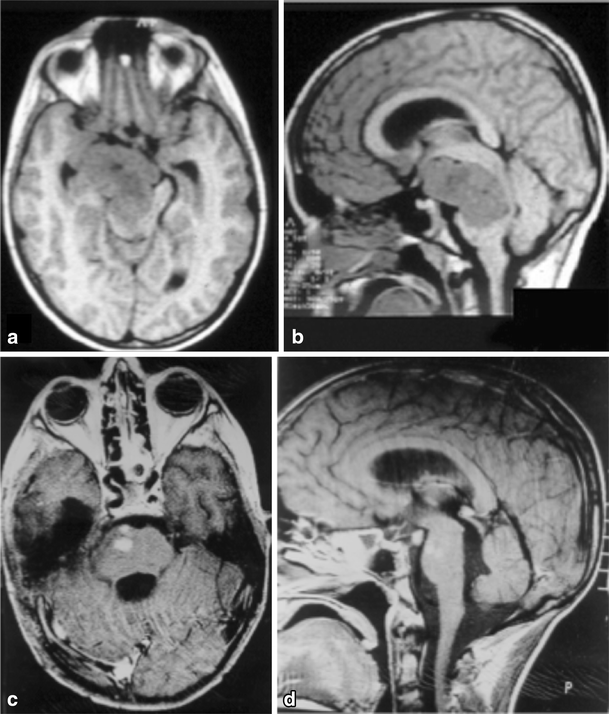

Fig. 4

a, b 4-year-old girl admitted with a right Weber Syndrome with a solid/cystic anterior mesencephalic lesion with expansion towards the interpeduncular cistern. c, d 6-year follow-up showing total resection by fronto-orbito zygomatic approach (pilocytic astrocytoma)

a, b A solid cystic tumor at the central portion of the midbrain with gadolinium enhancement growing towards the pineal region was removed by a central infratentorial supracerebellar approach. c, d 10-year follow-up shows no evidence of the lesion, which was a pilocytic astrocytoma

a Lateral view of the midbrain. The lateral mesencephalic sulcus (LMS) runs on the surface of the midbrain extending from the medial geniculate body (MGB) above to the pontomesencephalic sulcus (Pont. Mes. Sulc.) below. The LMS extends along the lateral edge of the medial lemniscus (ML). b The ML divides the midbrain into ventral (anterior) and dorsal (posterior) parts. Neurocritical structures at entry through the LMS are the corticospinal tract in the anterior midbrain, the red, oculomotor and trochlear nuclei in the central (tegmentum) midbrain, nuclei of the superior and inferior colliculus in the posterior (dorsal) midbrain. The oculomotor nucleus is positioned at the level of the inferior half of the superior colliculus and superior half of the inferior colliculus in the midline, and the trochlear nucleus is positioned at the level of the inferior half of the inferior colliculus in the midline. c Lateral lesion in the central midbrain approached via infratentorial supracerebellar route along the lateral sulcus of the mesencephalon. d Five-year follow-up after complete resection showing no evidence of the lesion, a pilocytic astrocytoma